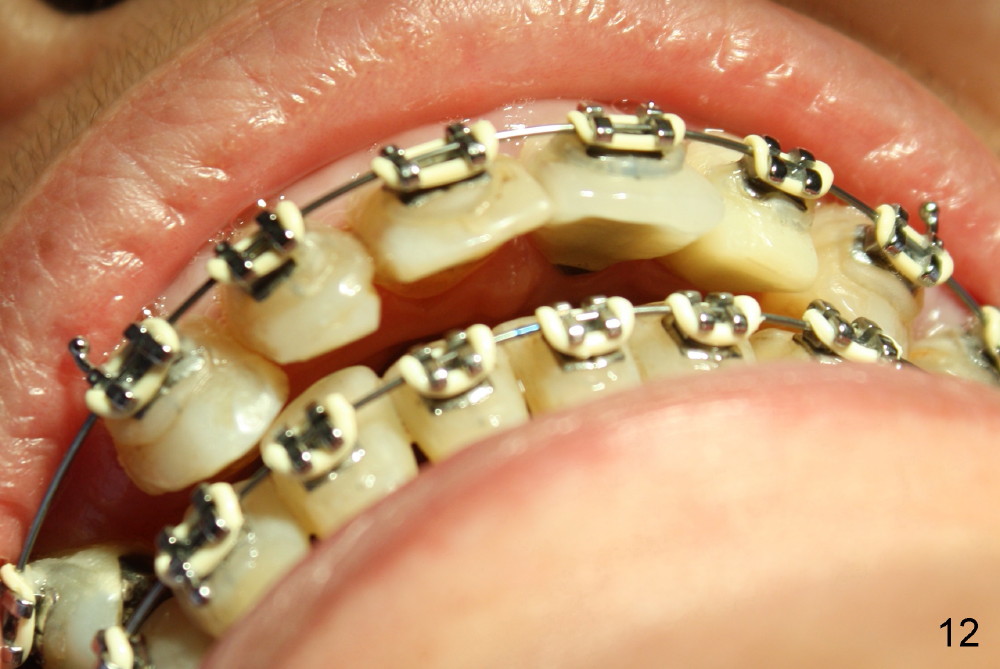

A prominent feature of implant failure in this case is pain. The patient feels that the pain is from the base of the nose. PA taken 3 days postop shows that the implant is inferior to the nasal floor (Fig.2 red ^). Clinically, the buccal gingiva continues to be erythematous 10 days postop (Fig.1). The pain is so unbearable that the implant (3.8x14 mm) is removed 10 days post placement. After repeated debridement, a 4.1 mm tap (Fig.3 T) is manually inserted with torque. A 4.1x14 mm submerged implant is placed with insertion torque < 30 Ncm, but it is placed subcrestally (Fig.4 <--). This time an immediate provisional is not provided. The flap is sutured. The pain disappears immediately. No infection is found 7 days postop (Fig.5). However, an asymptomatic vesicle is noted at the crest 3 weeks postop (Fig.6). The gingiva looks normal 2 and 3 months postop (Fig.7,8). The coronal gap dissolves 3 months postop (Fig.9 >, as compared to Fig.4), suggesting osteointegration. The implant is uncovered 4 months postop (Fig.10). Bracket is placed 5 months postop (Fig.10'). One month later, the left central incisor improves in position coronocervically (Fig.11), but the overjet needs correction by distalization of the upper anterior teeth. The implant at the site of #10 may be used as an anchorage.